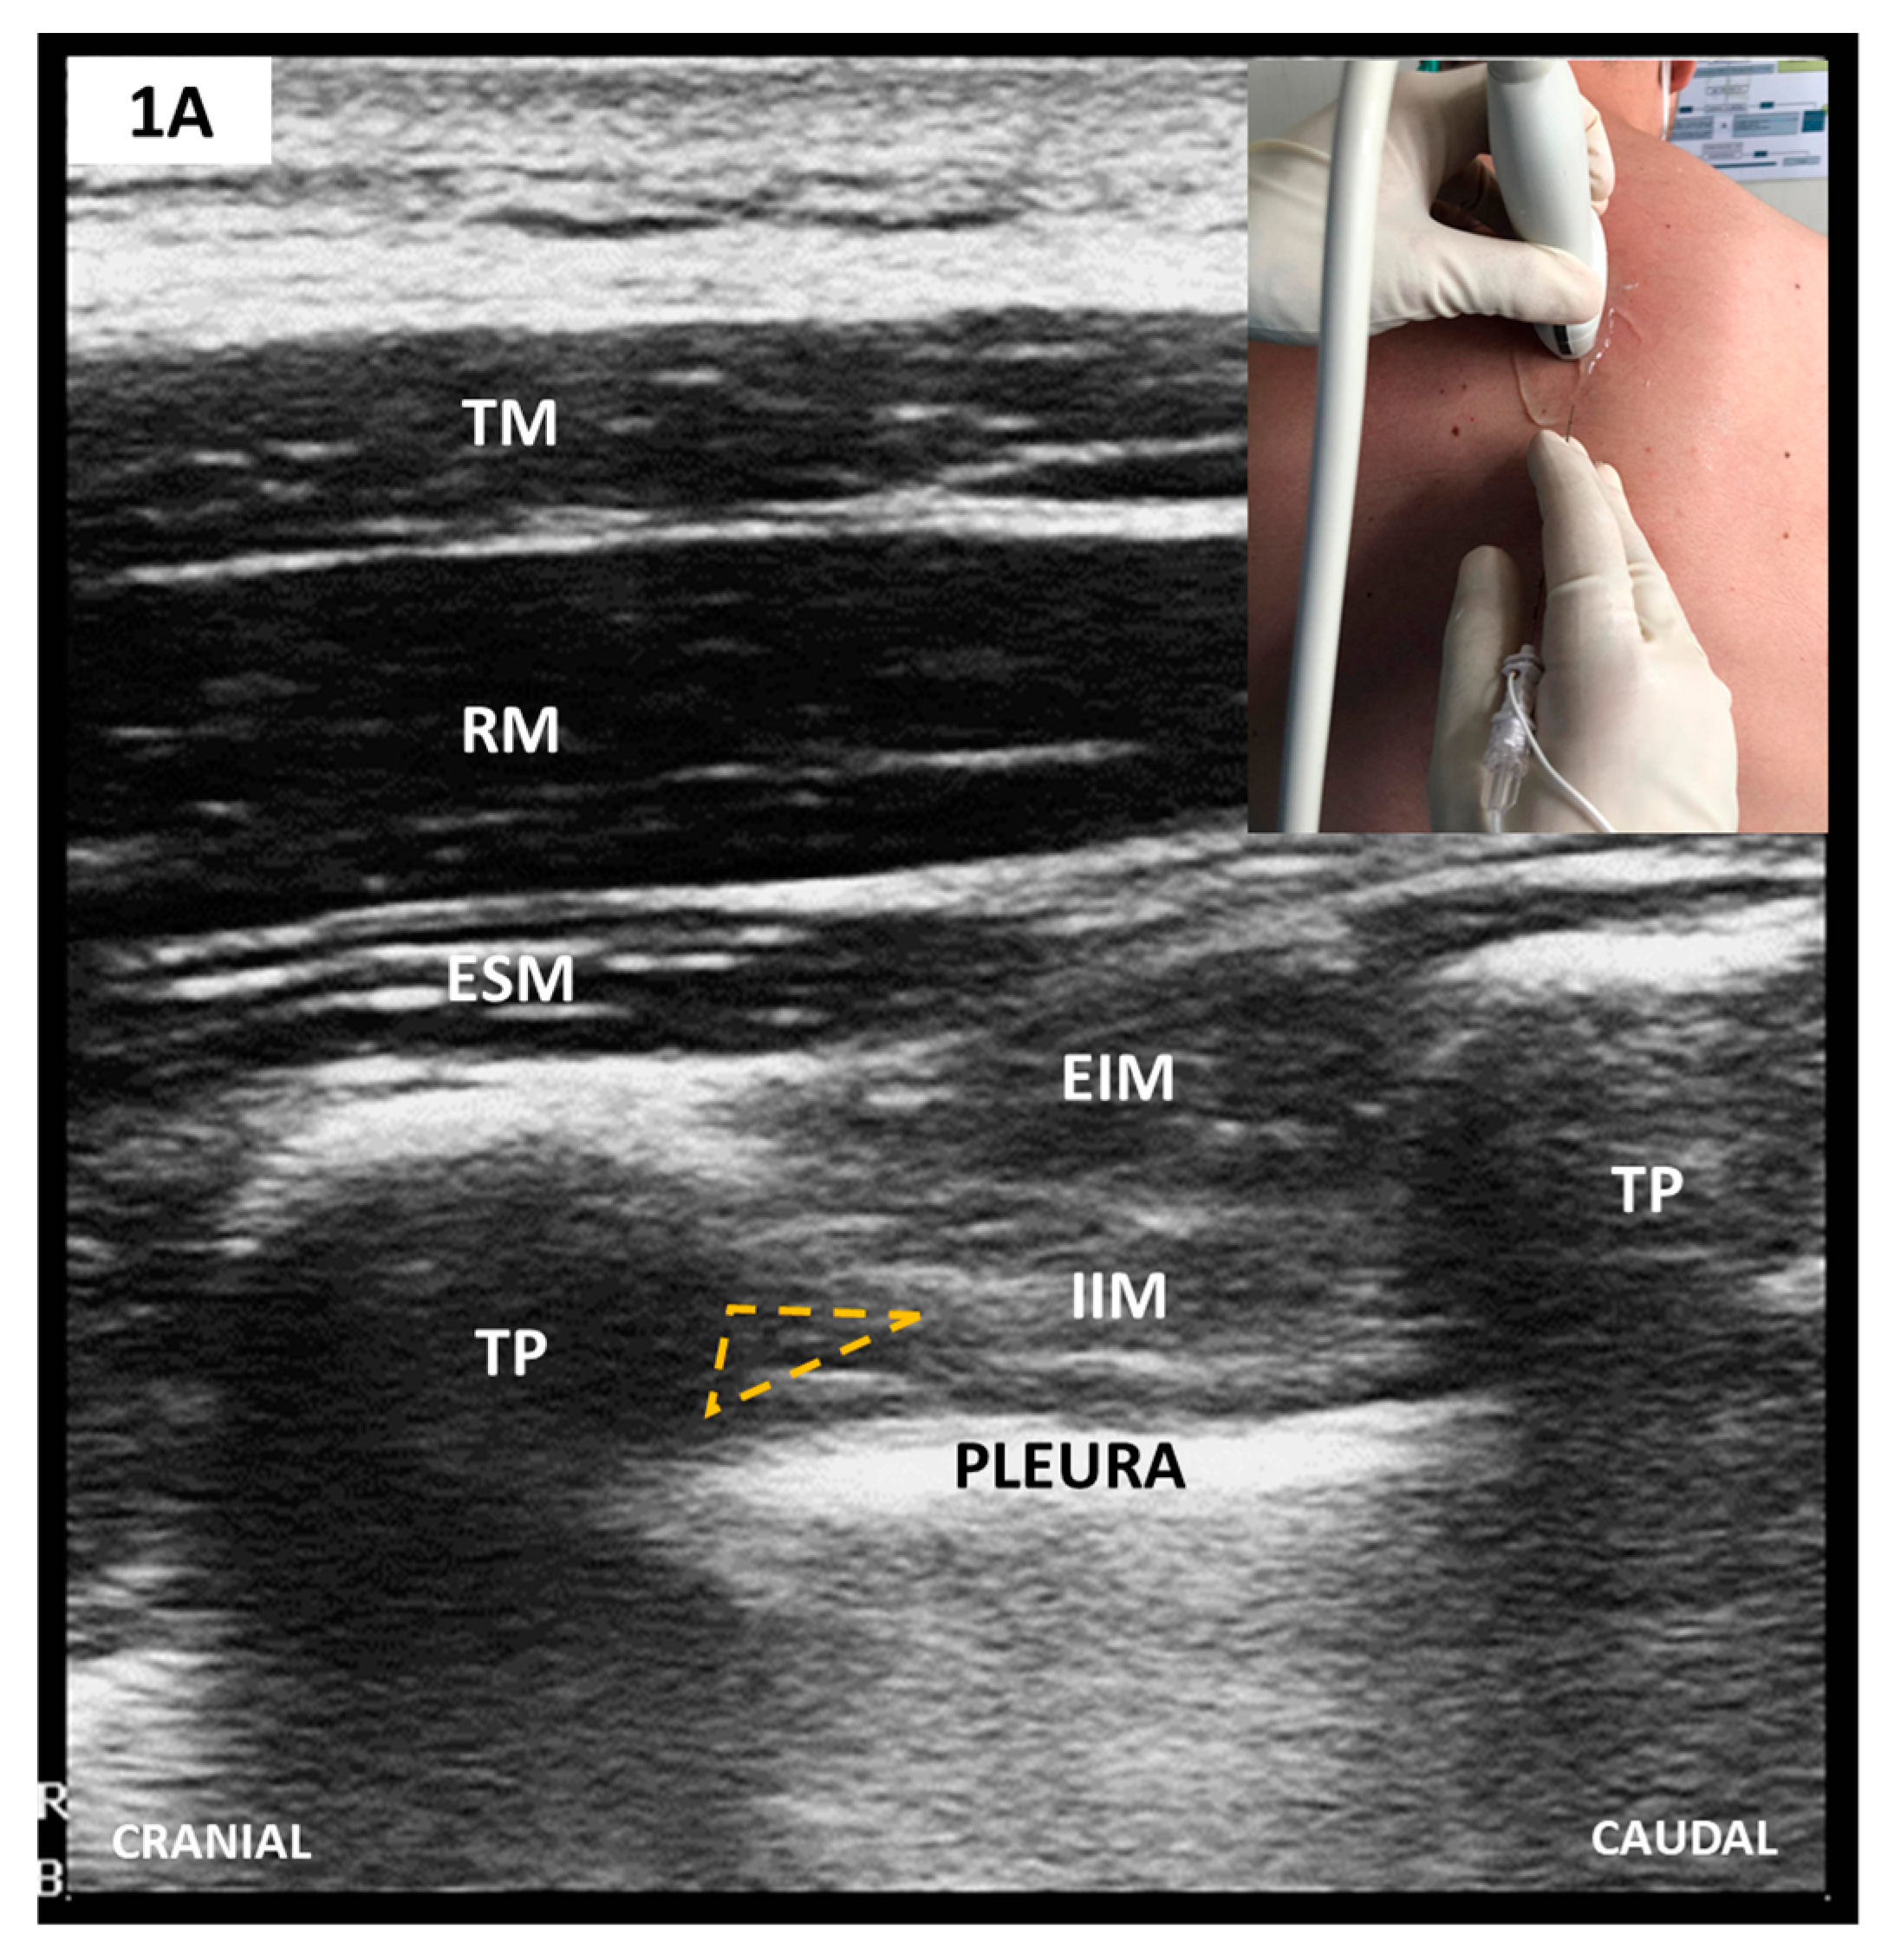

Sonoanatomy and Block Techniques (Figure 1)